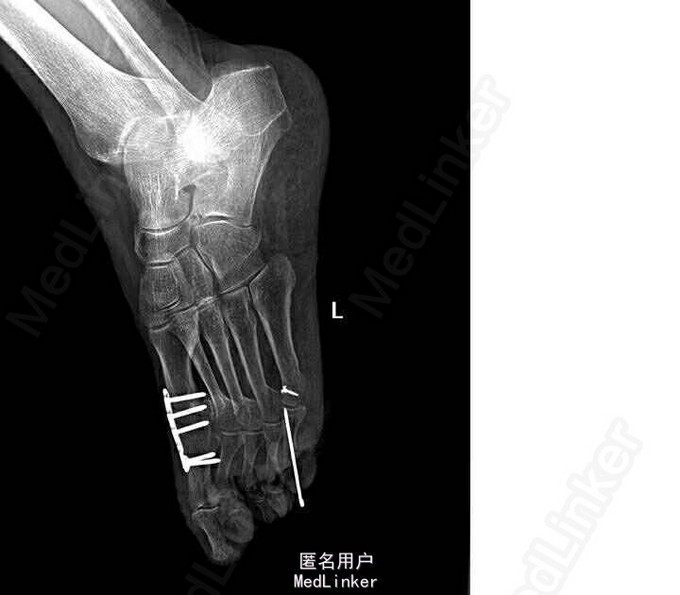

诊断:双侧扁平足(左侧重),左足截骨矫形术后,左足第一、五跖趾骨关节炎 局麻下行“左足矫形术(第五趾间关节融合内固定,第一、三、五趾骨屈肌腱松解,第一趾骨伸肌腱紧缩术)”。

术后行走疼痛明显改善,规律复查